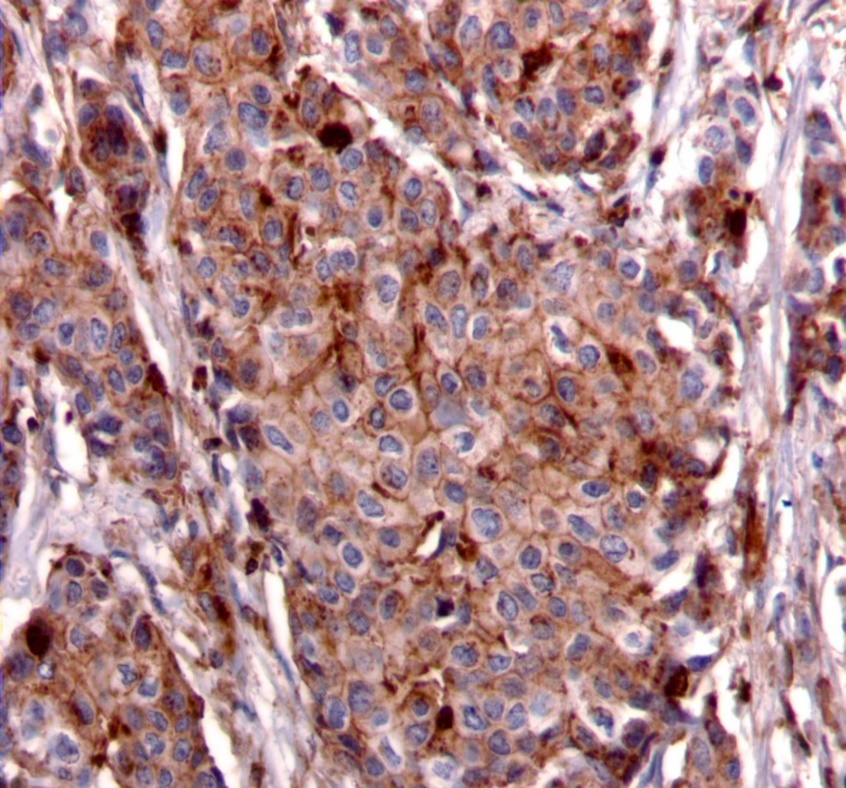

We used the following histologic criteria for IRS-1 and IRS-2 staining patterns which are outlined in a previous study.13 For IRS-1, a nuclear pattern was defined as diffuse nuclear staining (Figure 1). IRS-2 staining patterns were defined using the following criteria: Diffuse cytoplasmic staining was defined as evenly distributed cytoplasmic reactivity (Figure 2); punctate cytoplasmic staining was defined as clearly demarcated puncta of staining within the cytoplasm (Figure 3); and membrane staining was defined as focal or diffuse membranous staining (Figure 4). Sections of normal pancreas and normal breast tissue were used for positive and negative controls. The pathologists assessing staining patterns were blinded to the tumor recurrence score and all other data at the time of assessment.

Figure 4.Membranous staining pattern for IRS-2. (IRS-2 immunohistochemical stain, 200x magnification)